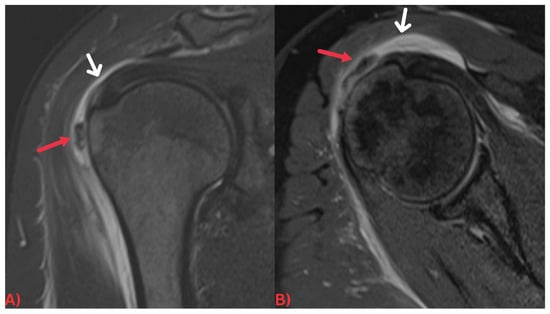

Specifically, MRI images display hydroxyapatite deposits as regions with low signal intensity across both T1- and T2-weighted images, attributable to the high mineral content of hydroxyapatite, a form of calcium phosphate crystals [27]. Consequently, this results in its manifestation in MRI images (Figure 3). Concurrently, MRI also reveals inflammation signs within surrounding soft tissues, such as edema and increased signal intensity on T2-weighted images [28] (Figure 4). Edema, a common response to inflammation or injury, indicates the body’s reparative efforts, while a heightened signal intensity on T2-weighted images typifies inflammation and is present in several conditions, including HADD (Figure 5).

Figure 3. (A) Axial T2 fat-saturated MRI image and (B) sagittal PD fat-saturated MRI image of the left hip demonstrating a well-defined low signal intensity calcification at the insertion of the left gluteus medius tendon (red arrows) with surrounding soft tissue edema.

Figure 5. (A) Coronal PD fat-saturated MRI and (B) axial PD fat-saturated MRI images of the right shoulder demonstrating a few ill-defined low signal intensity calcifications (red arrows) in the subacromial/subdeltoid bursa, with fluid signal intensity within the bursa (white arrows) most suggestive of calcific bursitis.